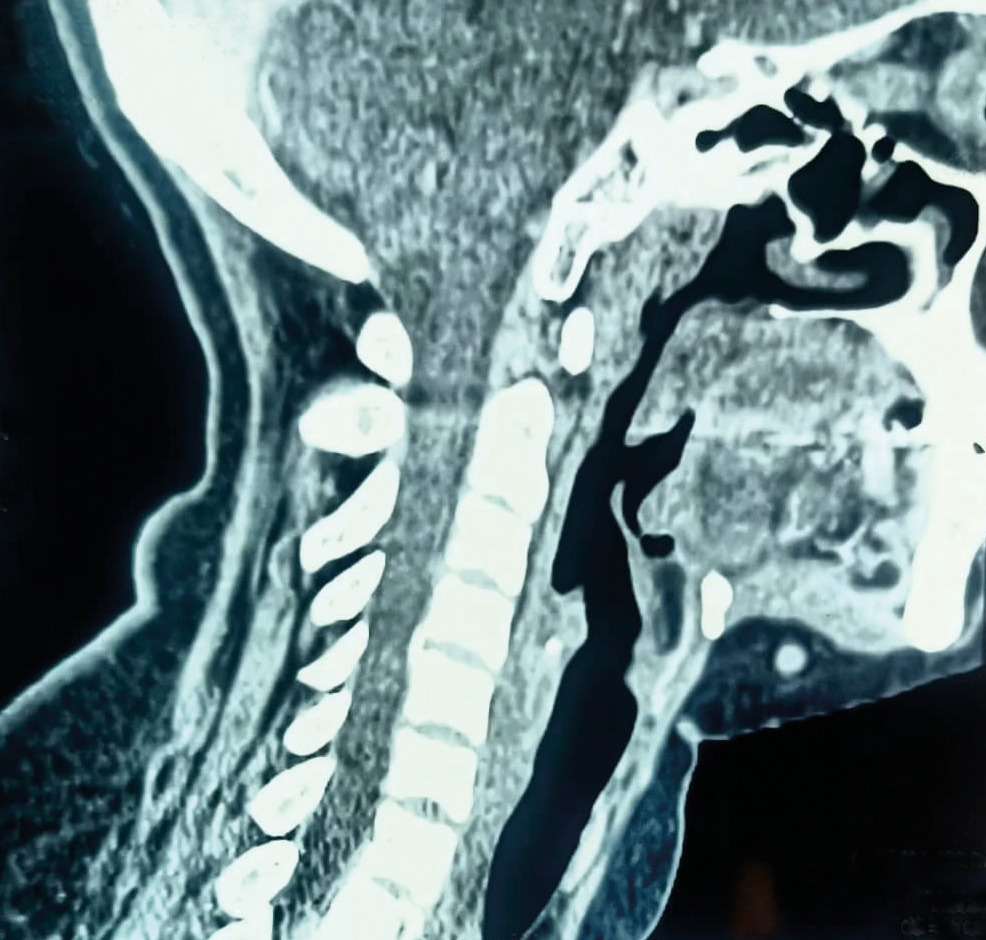

Une patiente âgée de 40 ans est admise à l’hôpital pour exploration d’adénopathies cervicales. L’interrogatoire révèle une obstruction nasale chronique accompagnée d’une rhinorrhée. L’endoscopie met en évidence une rhinite croûteuse avec un bombement du cavum (fig. 1). La tomodensitométrie montre un cavum pseudotumoral (fig. 2, 3 et 4). L’histologie objective un processus granulomateux tuberculoïde (fig. 5). Le GeneXpert sur fragment de biopsie, l’intradermoréaction à la tuberculine et la recherche de bacille de Koch dans les crachats sont négatifs.